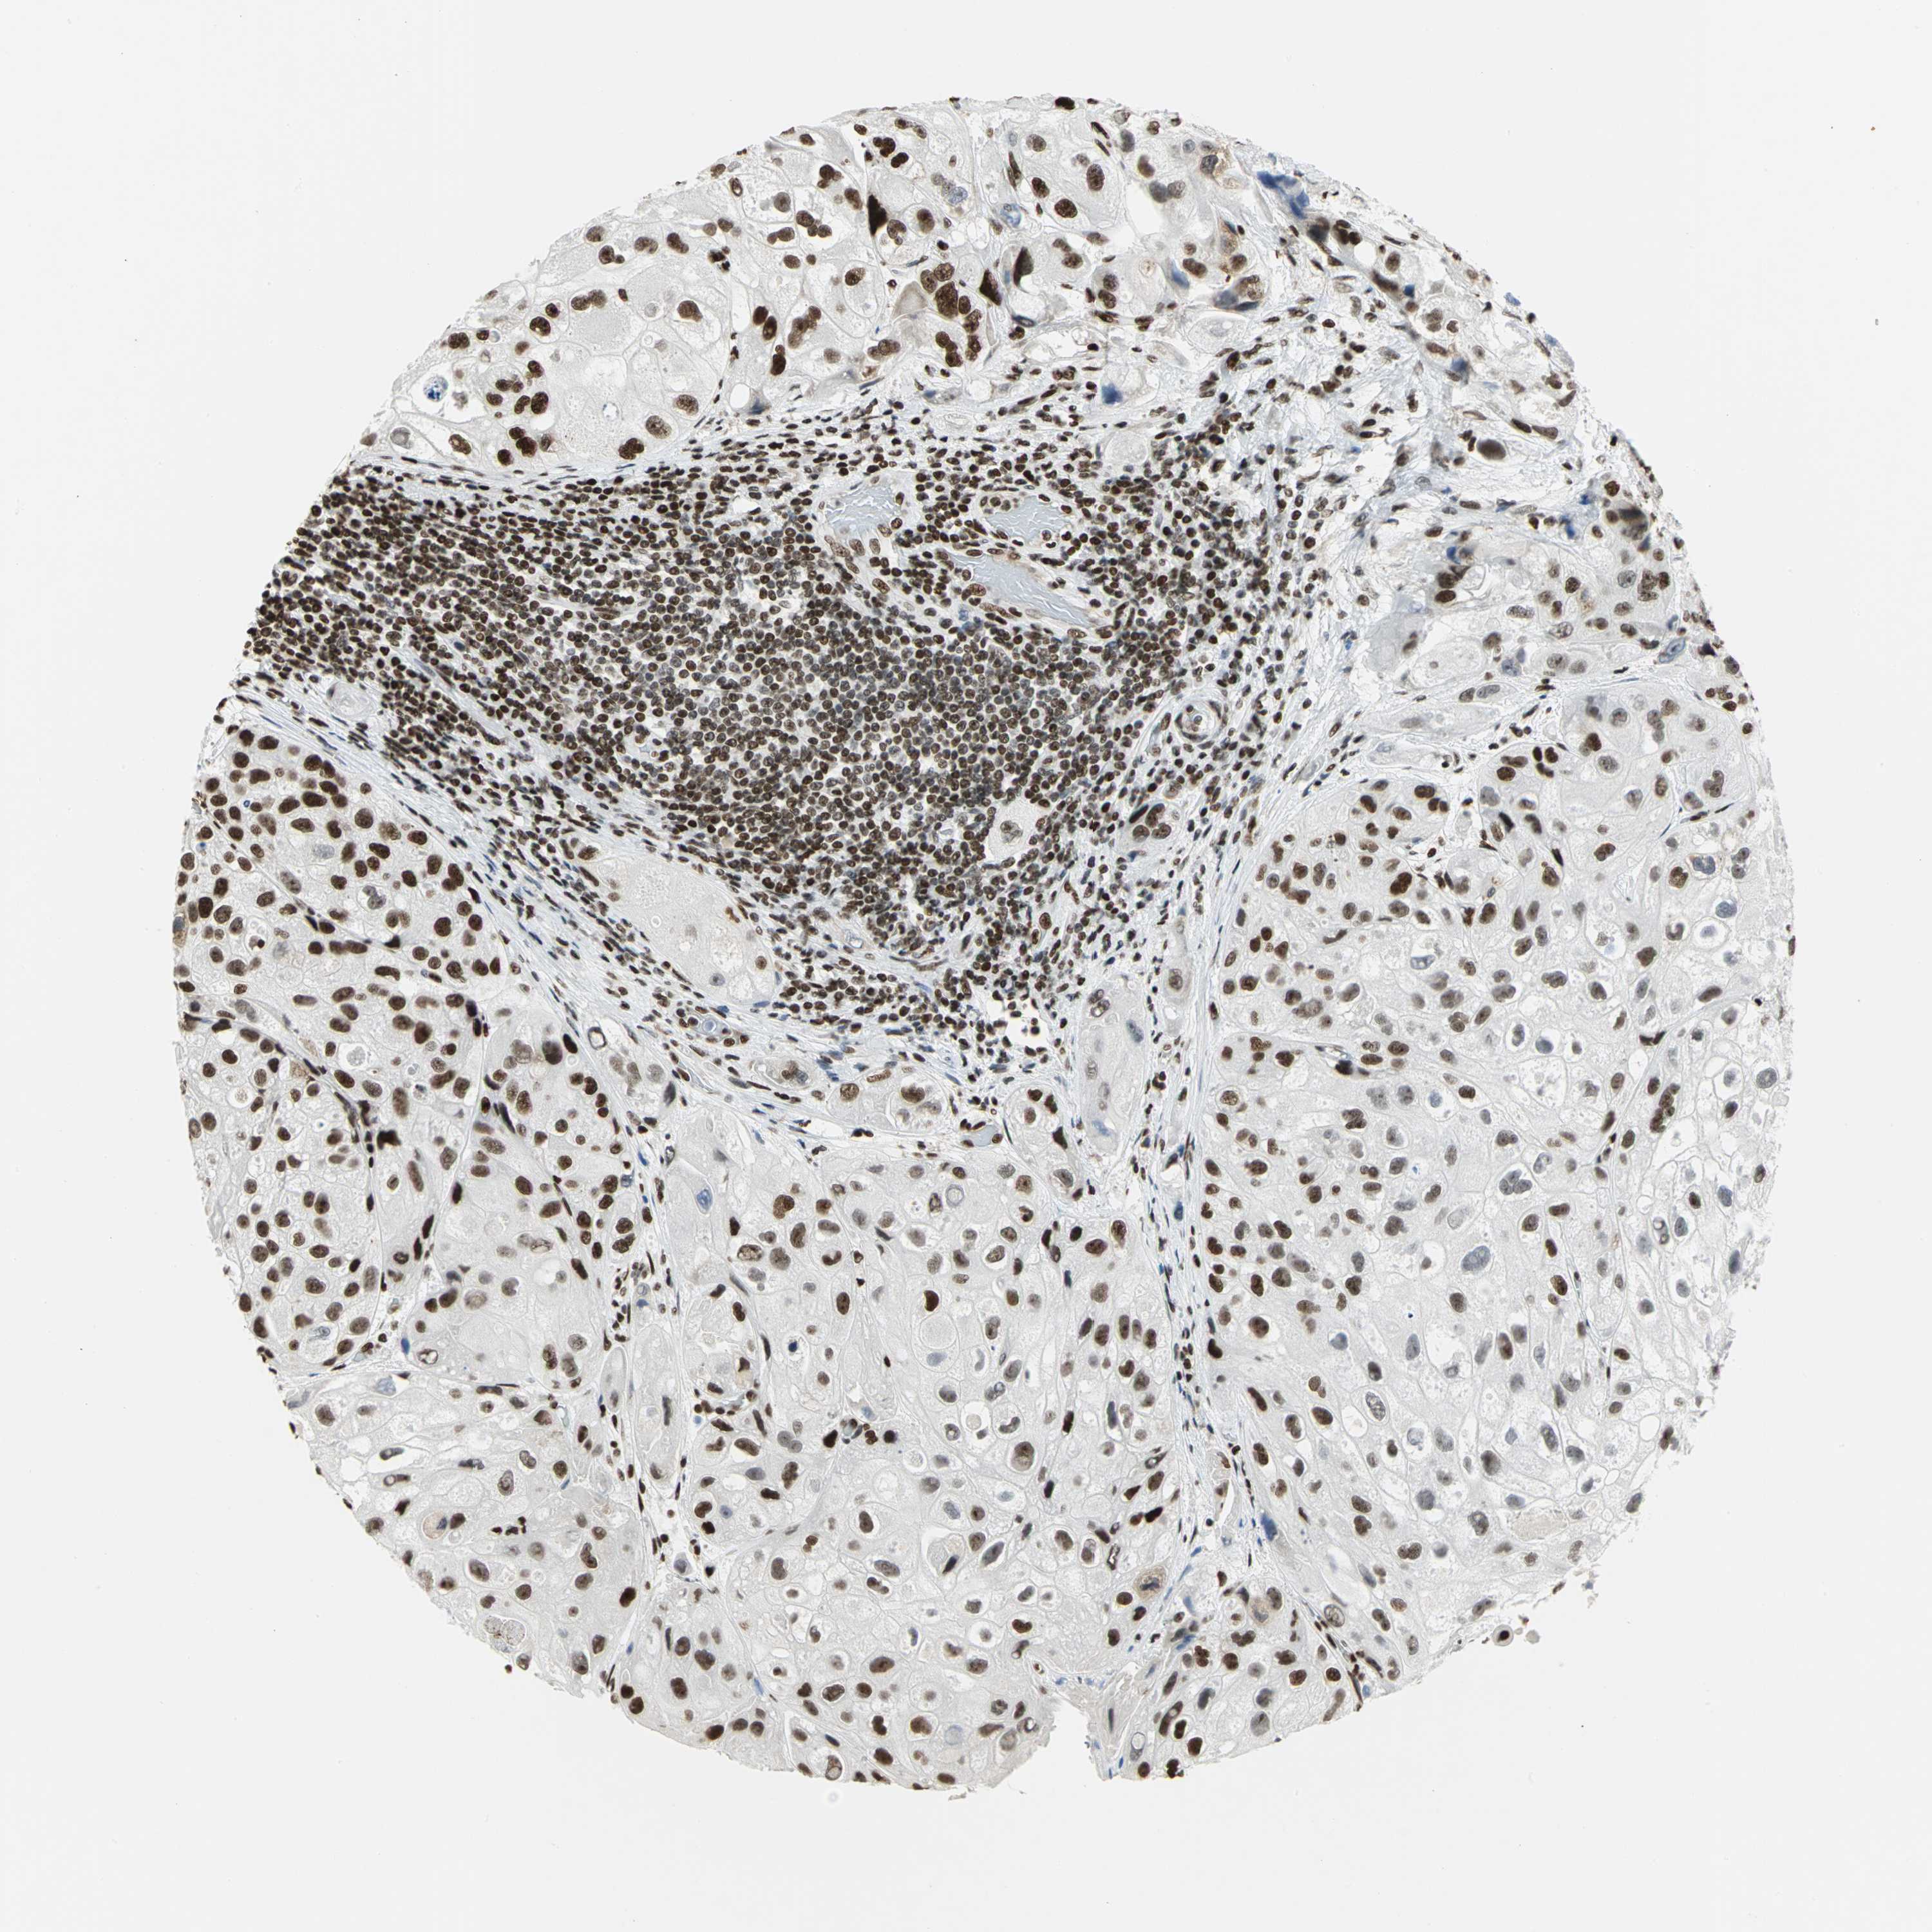

UROTHELIAL CANCER - Protein expressioni

A mouse-over function shows sample information and annotation data. Click on an image to view it in a full screen mode. Samples can be filtered based on level of antibody staining by selecting one or several of the following categories: high, medium, low and not detected. The assay and annotation is described here.

Note that samples used for immunohistochemistry by the Human Protein Atlas do not correspond to samples in the TCGA dataset.

Antibody stainingi

Antibody staining in the annotated cell types in the current human tissue is reported as not detected, low, medium, or high, based on conventional immunohistochemistry profiling in selected tissues. This score is based on the combination of the staining intensity and fraction of stained cells.

Each image is clickable and will lead to virtual microscopy that enables deeper exploration of all samples and also displays staining intensity scores, fraction scores and subcellular localization as well as patient and tissue information for each sample.

Antibody HPA003506

Antibody CAB005873

Staining

High

Medium

Low

Not detected

Intensity

Strong

Moderate

Weak

Negative

Quantity

>75%

75%-25%

<25%

None

Location

Nuclear

Cytoplasmic/membranous

Cytoplasmic/membranous,nuclear

Urothelial carcinoma, High grade

Urothelial carcinoma, Low grade